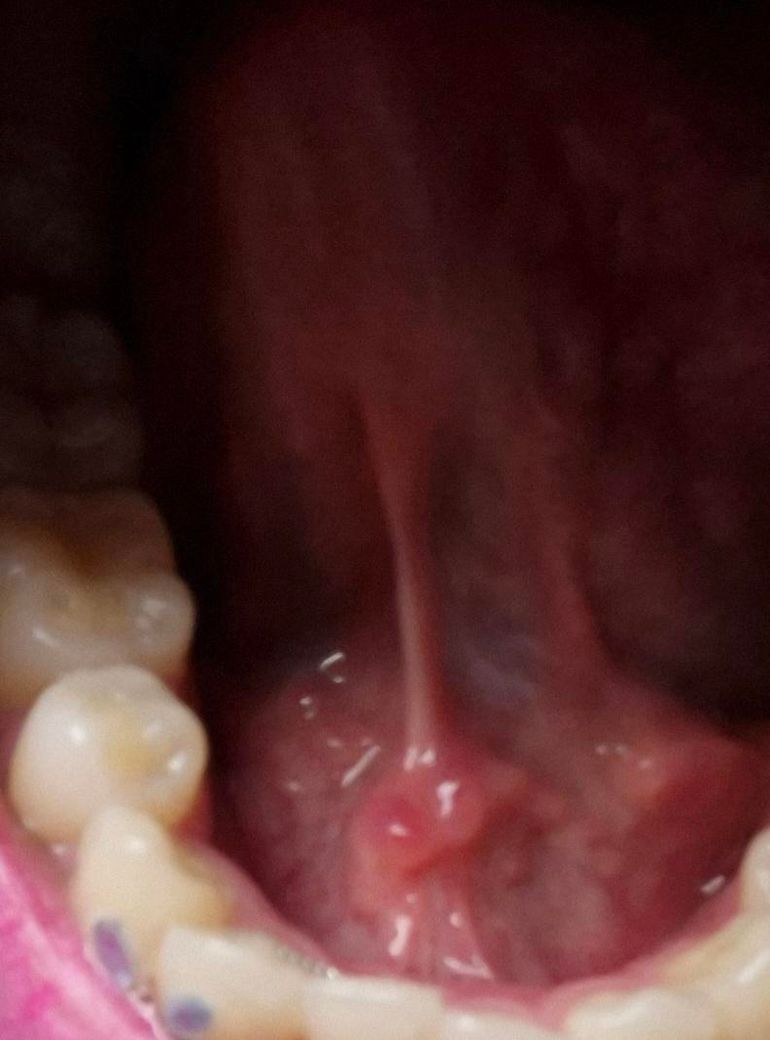

입 혓바닥쪽에 뭐가 잇는거 같아요 심지어 안쪽에 구내염도 생긴거같아요

사진과 같이 혀 바로 안에 길쭉한 기둥같은 곳에도 뭐가 저렇게 붉게 있고요 안 쪽에도 구내염처럼 아파요ㅠㅠ 보려고했는데 잘 안 보이구요 뭘까요

설소대 부위에 자극을 받아서 생긴거 같습니다. 최대한자극이 가지 않도록 하시고 통증이 잇다면 진통제를 드시고 시간이 지나면 괜찮아 지실꺼에요.

사진으로 봤을 경우에는 크게 문제가 보이진 않습니다. 하지만 해당 부위에 불편감이 있거나 구내염이 있다면 몸의 면역력이 떨어져 있을 가능성이 높습니다.

충분한 휴식을 취해주시고 그래도 증상이 없어지지 않는다면 치과의 구강내과에서 진료를 받아보는 것을 권유드립니다.

염증의 양상이 다소 있는 것으로 사진상 관찰됩니다 구강내과가셔서 정확한 진단 받아보시기 바랍니다